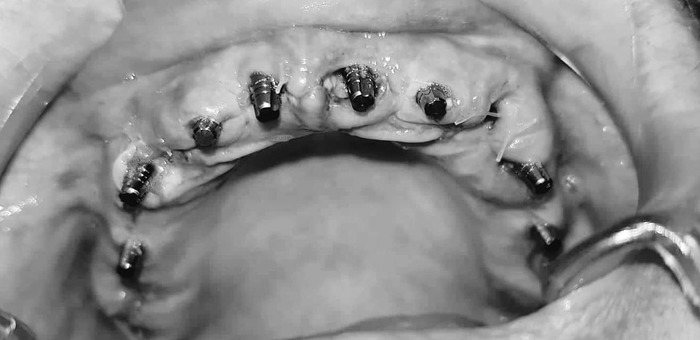

Теперь про операцию - она проходила под местным обезболиванием, была именно операцией - я был в халатике и на лице - салфетка с дыркой напротив рта. Седации никакой не было - Георгий сказал, что он это не практикует. Имхо - его личное дело. Была толпа народу - сам Георгий, Хатуна, Гоча и еще один дядька, который хирург и, видимо, учился у Георгия, и пара медсестричек. Георгий сам удалял зубы и потом вкручивал импланты.

Я устал, обезболивание отходило неравномерно и последний час раны ныли и я уже на волевых держался; Хатуна наложила швы, я сел и понял, что меня трясет. Трясло минут 10 - мне дали таблетку обезболивающего, типа кеторола, отпоили валерьянкой, два раза померили давление - и только через полчаса отпустили в номер. В гостинице я принял свою любимую таблетку - темпалгин, и как только ноющая боль стихла - бухнулся спать. В 5 вечера зашел Георгий - я к тому времени уже проснулся - и отправил меня в рентген-кабинет и в аптеку - за антибиотиками и мазью Романадзе. Ну, то есть, после двух часов сна я уже был вменяем и у меня ничего не болело, только ныло на отходняках. Мазью я смазывал свежесделанную капу - она типа для заживления ран и все такое - и одевал капу на ночь и в свободное от еды время.

Вот снимки через 5 часов после операции: